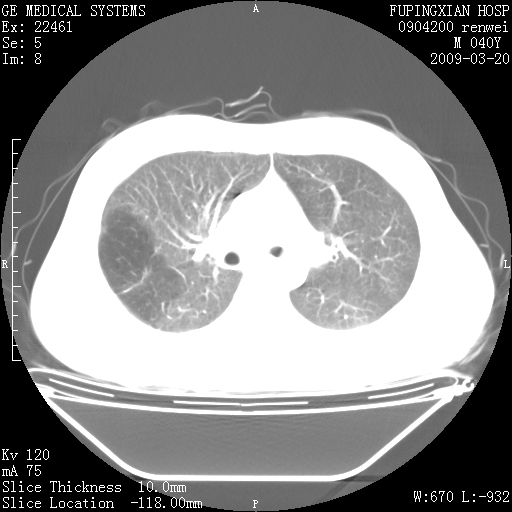

标题: CT18920:平时体健,体检时发现以下问题。 [打印本页]

标题: CT18920:平时体健,体检时发现以下问题。

单侧肺气肿表现,原因?   特发性或先天性可能

右肺气肿。

右肺局限性肺气肿

右肺局限性肺气肿。

右肺局限性肺气肿,有无呛咳史?

双肺弥漫磨玻样改变,肺纹理增重,考虑早期间质纤维化伴局部阻塞肺气肿,[考虑黏液栓]

右肺局限性肺气肿;[考虑黏液栓]所致。

双肺弥漫磨玻样改变,右肺局限性肺气肿。病人没有症状?

考虑间质性肺炎伴右侧局限性肺气肿,

先天性支气管闭锁

右肺局限性肺气肿,原因?先天支气管闭锁?粘液栓?